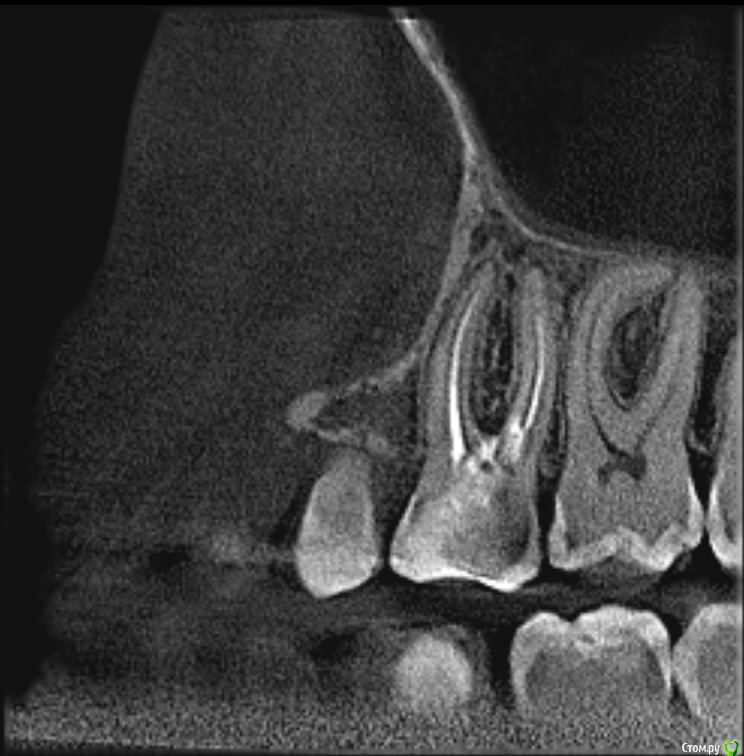

Demon_L Опубликовано 23 января, 2020 Поделиться Опубликовано 23 января, 2020 (изменено) Мне 36 лет, примерно 12 лет назад залечивал зуб (верхняя левая 6-ка), запломбировали 3 канала гуттаперчей, поставили обширную световую пломбу в хорошей платной клинике.Позже я стал замечать, что зуб немного темнее остальных, но не придавал этому значения, т.к. зуб не беспокоил. На днях откололся небольшой кусочек от этого зуба, пошел в клинику, сделали снимок КТ, сняли пломбу. Вердикт - 3 канала не требуют перелечивания, но есть 4-й канал, который требует лечения и который не нашли первый раз. Но что самое печальное - обнаружили перфорацию дна полости, которую по ошибке сделали при первом лечении, видимо когда искали 4-й канал. Тогда же видимо и положили раствор резорцин-формалина, что и придало темный с отттенками красного цвет зубу.Пока не нашли перфорацию, по снимкам склонялись к установке коронки, но после того, как обнаружили, один врач настойчиво рекомендовал удаление и имплантат, другой допускает коронку, но тоже рекомендует имплантат.Хотел бы спросить Вашего мнения, действительно ли при наличии перфорации дна полости (она небольшая, но файл в неё проходит и выступает капелька крови) ставить коронку противопоказано?Можно ли сначала залечить перфорацию, а потом ставить коронку? Прибегать к удалению и имплантации хотелось бы в последнюю очередь.Прилагаю несколько снимков КТ. Если они недостаточно информативны, готов выложить с любого другого ракурса. Могу вообще поделиться isо-файлом со снимком (образ CD), тогда можно будет покрутить в 3D как угодно у себя на ПК (запускается автоматически без установки чего-либо).Заранее спасибо за консультацию. Изменено 23 января, 2020 пользователем Demon_L Ссылка на комментарий

Дмитрий Л. Опубликовано 29 января, 2020 Поделиться Опубликовано 29 января, 2020 (изменено) Не соглашусь категорично. По кт там даже четвертый канал искать не надо. У вас 12 лет пролеченный зуб без проблем стоит. Темный цвет и скол решается коронкой.Риск трещины зуба есть. Этого зуба и любых других. Все удалить?Непонятно зачем перфорацию заново раскрыли. Идите в другую клинику, просите закрыть перфорацию и ставьте новую пломбу. Или коронку*Это вывод из ваших слов и приложенных срезов. Изменено 29 января, 2020 пользователем Дмитрий Л. Ссылка на комментарий